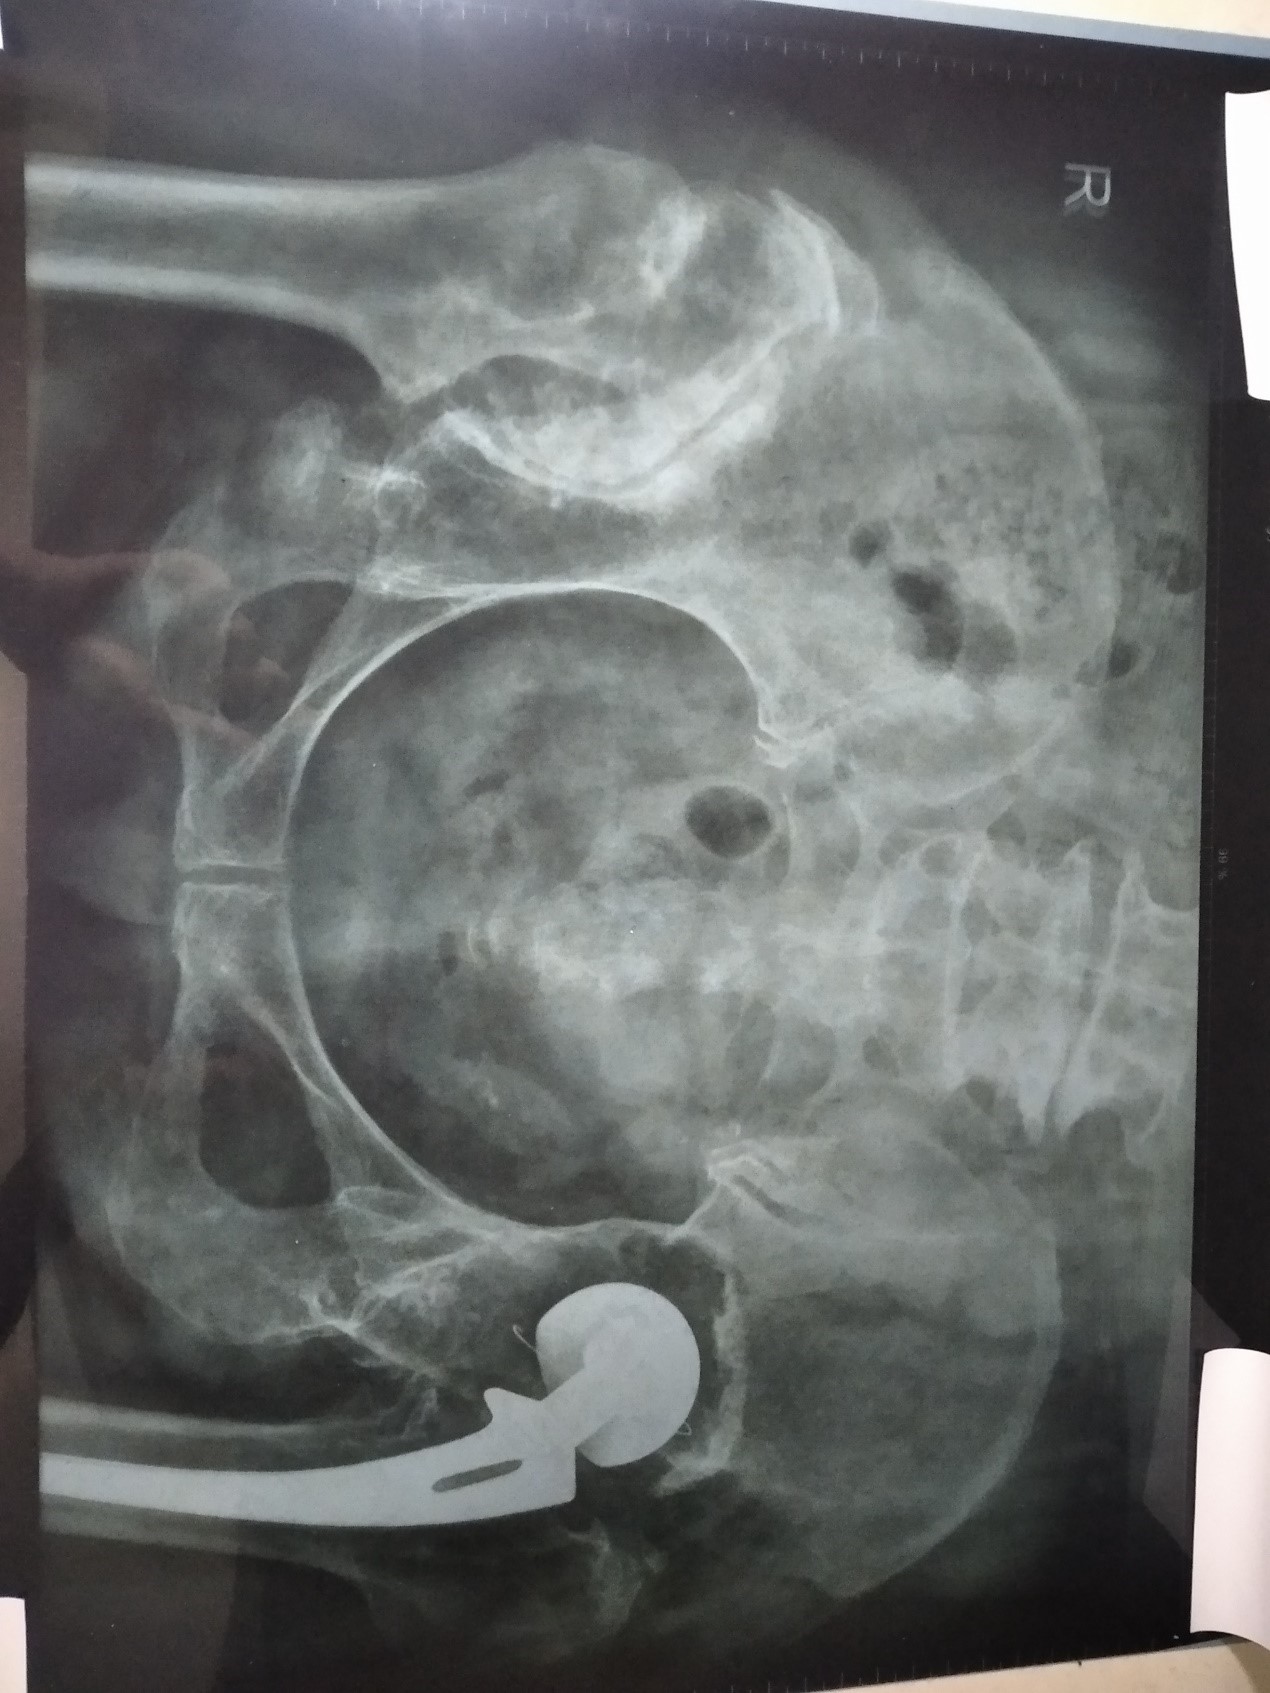

今年三月二十一日到医院拍了一个片子,我把DX影像诊断报告单抄写如下:

检查项目:骨盆IR:骨盆(正位)

影像表现:显示右髋关节髋臼变浅,密度增高,股骨头上移位,形成假关节,股骨头扁平宽大,密度增高。左髋关节人工关节置换术后,余各骨质结构良好,骨小梁清晰,关节间隙正常,关节面光整。

通过片子看,右侧髋关节是形成了假关节,所以我右侧的髋关节脱位的问题解决了。而且活动范围扩大,持重力增强,整个腿也归正了,身体也直了。我整个身体以前是向右侧弯曲的,所以左侧髋关节也向外突出。现在右腿恢复了以后,身体变直了,左侧关节也進去了,而且膝关节也逐渐的消肿、变直,整个左腿正常健康了。

法轮大法在我身上创造了两个奇迹:一个是我左侧一九九二年做过手术的髋关节,到现在已过三十一年了,超过医生讲的保持好能挺二十年的说法,而且髋关节比以前更好;第二个奇迹是我没做手术的右侧髋关节,本已脱位变形长骨刺,却在大法修炼中痊愈了,这更是神奇超常的。